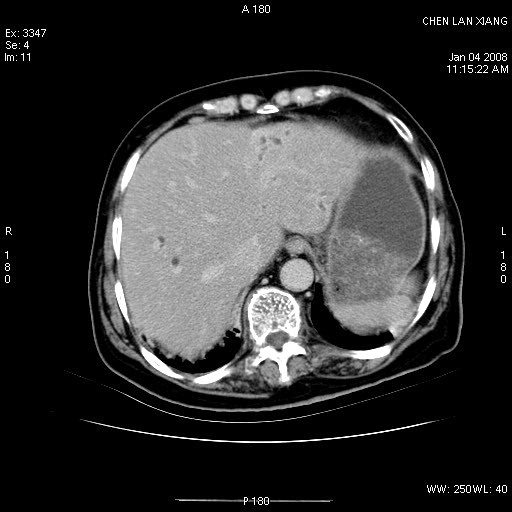

女,76岁,腹痛3-4天,b超示:肝内实性肿物,胆囊强回声,胆总管扩张.

考虑:1、胆总管下端结石伴梗阻性肝内外胆管扩张(肝左叶外侧段肝内胆管多发结石、胆管炎);

2、肿囊癌累及肝,不除外 黄色肉芽肿性胆囊炎。

1 胆总管末端结石伴肝内胆管结石,肝内外胆管扩张。2 胆囊扩大,胆囊壁不规则增厚,内见软组织密度影。考虑:慢性胆囊炎,不除外胆囊癌!

ct所见:1、 肝内胆管结石,肝内外胆管扩张。低位胆道梗阻,胆总管下端结石;2 胆囊扩大,胆囊壁不规则增厚

考虑:胆总管下端结石并肝内外胆管扩张,肝内胆管结石;

标题: 肝右叶病灶

胆囊癌侵犯肝右叶?

1)胆囊癌伴肝脏转移。2)胆总管下端结石、肝内胆管结石伴肝内外胆管扩张。